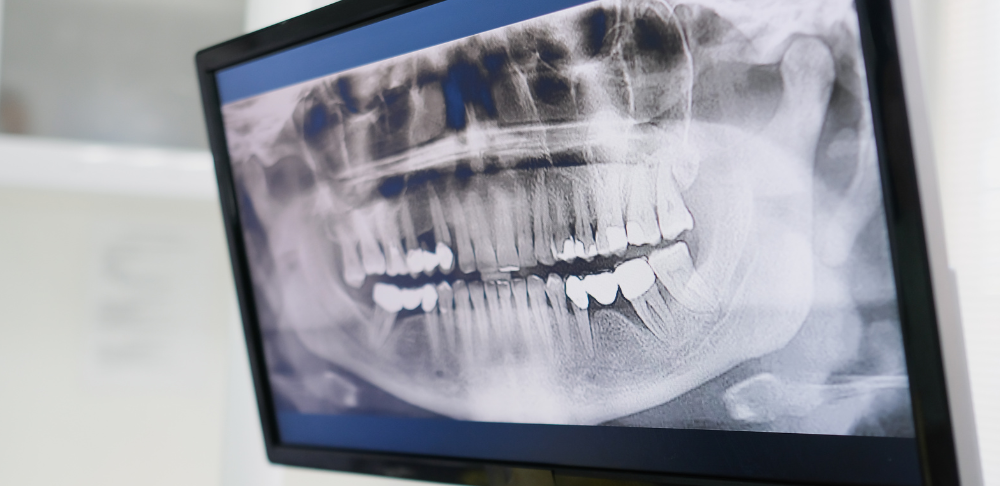

RTG zębów to badanie obrazowe, które pozwala lekarzowi zobaczyć struktury niewidoczne podczas standardowego badania jamy ustnej. Zdjęcie rentgenowskie pokazuje nie tylko same zęby, ale również ich korzenie, kość, zatoki szczękowe oraz okolice wierzchołków korzeni.

Dzięki RTG możliwe jest wykrycie próchnicy ukrytej między zębami, zmian zapalnych, torbieli, pęknięć korzeni czy problemów, które nie dają jeszcze objawów bólowych. To właśnie dlatego diagnostyka RTG jest tak ważna dla skutecznego i bezpiecznego leczenia.